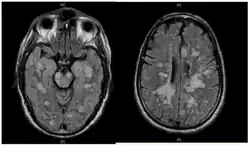

Fulminating ADEM showing many lesions. The patient survived, but remained in a persistent vegetative state